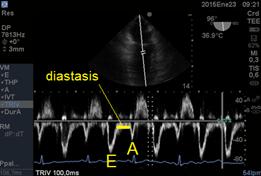

Con doppler pulsado (en imágenes medioesofágicas de 4 y 2 cámaras) podemos analizar la característica del flujo que atraviesa la válvula y podemos valorar integralmente la diástole cardíaca izquierda(14). Luego de un tiempo normal de relajación isovolumétrica (TRIV) cuyo valor normal es de 150 a 240m/s, es el tiempo de comienzo de la díastole fisiológica, es decir de la relajación ventricular, donde la válvula aórtica ya se cerró y aún no se abrió la mitral. Cuando se abre la válvula mitral se genera la onda E ,de llenado temprano, cuyo valor normal es entre 50 y 80cm/seg. Luego las presiones entre la aurícula y el ventrículo se igualan, deja de pasar sangre,este periodo se llama Diastasis. (Figura 12) Para finalmente la aurícula izquierda en su función de bomba generar la diástole tardía a través de la onda A.

Figura 12: imagen de 2 cámaras medioesofágico (96°) con Doppler Pulsado onda E llenado diastólico rápido, diastasis y onda A de llenado lento por contracción auricular.